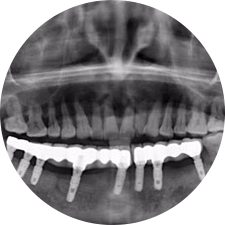

口腔種植是將人工牙根通過手術(shù)植入牙骨內(nèi),獲得牙槽骨牢固的支持,通過特殊的裝置和方式連接牙修復(fù)體,獲得與天然牙功能、結(jié)構(gòu)以及美觀相似的效果。

河北惟德口腔醫(yī)院擁有國(guó)內(nèi)豐富的半口/全口、即刻負(fù)重種植案例,十八年案例跟蹤分析,總結(jié)梳理出的各種不同類型的種植案例,Nobel種植體系針對(duì)半口/全口缺牙患者,通過4-8顆種植體可快速達(dá)到牙齒重建,不僅植入種植體較少,節(jié)省費(fèi)用,手術(shù)時(shí)間更短。

術(shù)前患者CBCT口掃1:1三維重建,模擬手術(shù)過程及預(yù)測(cè)術(shù)后治療效果,確定每顆植體植入的適合的種植位點(diǎn)、深度及角度,有效避免損傷頜骨重要解剖結(jié)構(gòu),提高手術(shù)準(zhǔn)確度與安全性。

惟德口腔種植體系是以患者感受為中心,取代傳統(tǒng)種植牙手術(shù)需要翻瓣、打孔、縫合,術(shù)前、術(shù)中、術(shù)后的繁復(fù)流程,采用3D導(dǎo)航微創(chuàng)準(zhǔn)確種植技術(shù),通過數(shù)字化CAD/CAM掃描技術(shù)獲得缺牙患者口腔數(shù)據(jù),以數(shù)據(jù)為基礎(chǔ)重建口腔模型進(jìn)行模擬種植。

術(shù)前將患者口內(nèi)的CBCT數(shù)據(jù)及咬合關(guān)系上傳到計(jì)算機(jī)中,建立1:1三維重建,模擬手術(shù)過程及預(yù)測(cè)術(shù)后治療效果,找出較佳種植位點(diǎn)、深度及角度,獲取實(shí)際種植體在頜骨內(nèi)的具體三維位置,有效避免損傷頜骨重要解剖結(jié)構(gòu),大大降低手術(shù)風(fēng)險(xiǎn),提升種植成功率。